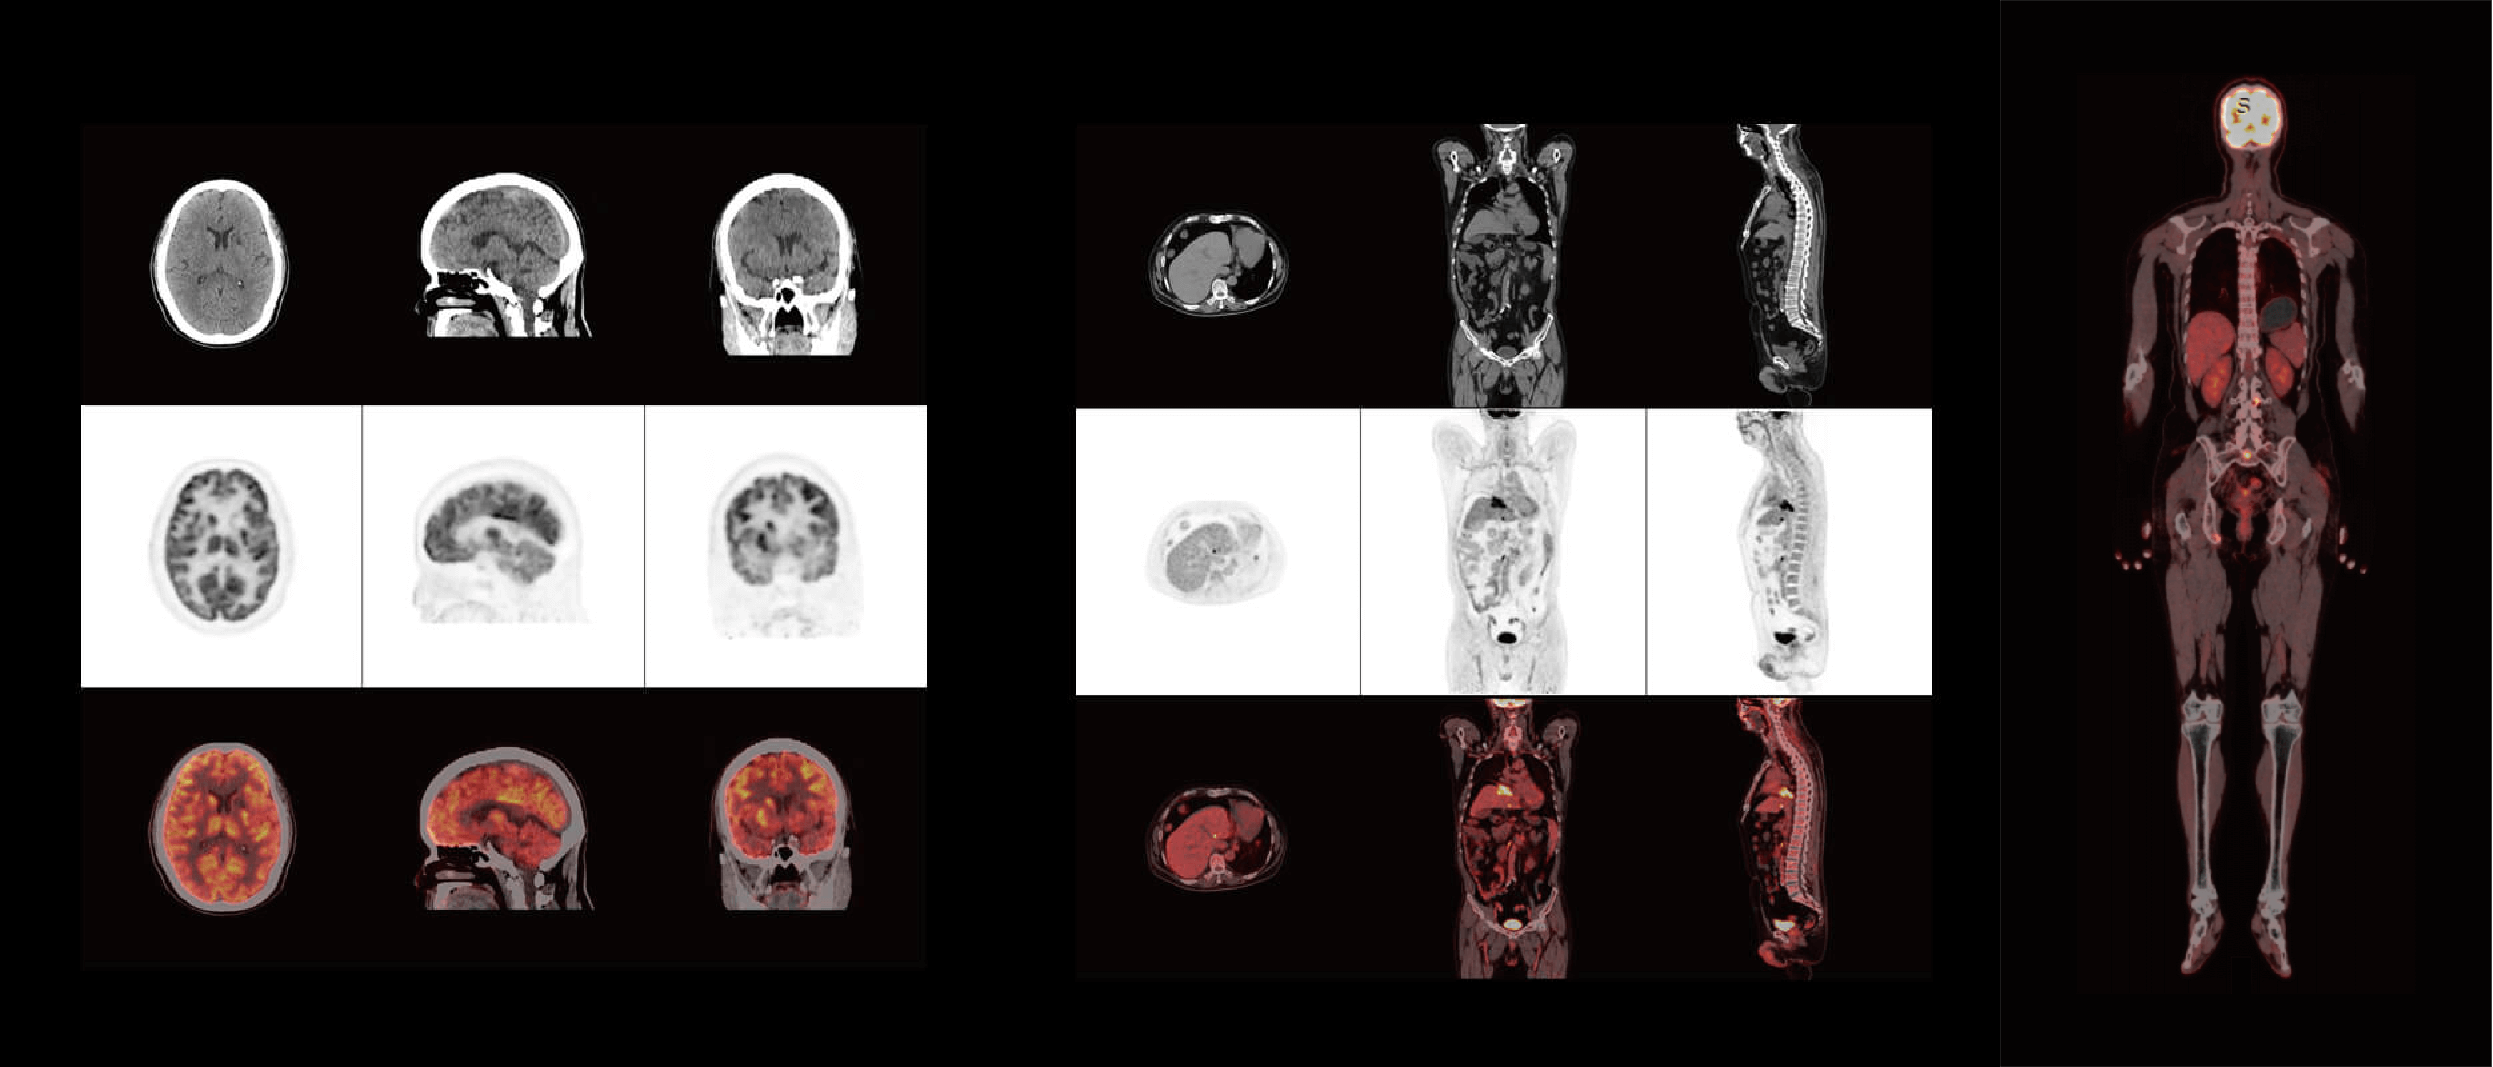

ScintCare PET/CT 730T

臨床畫廊